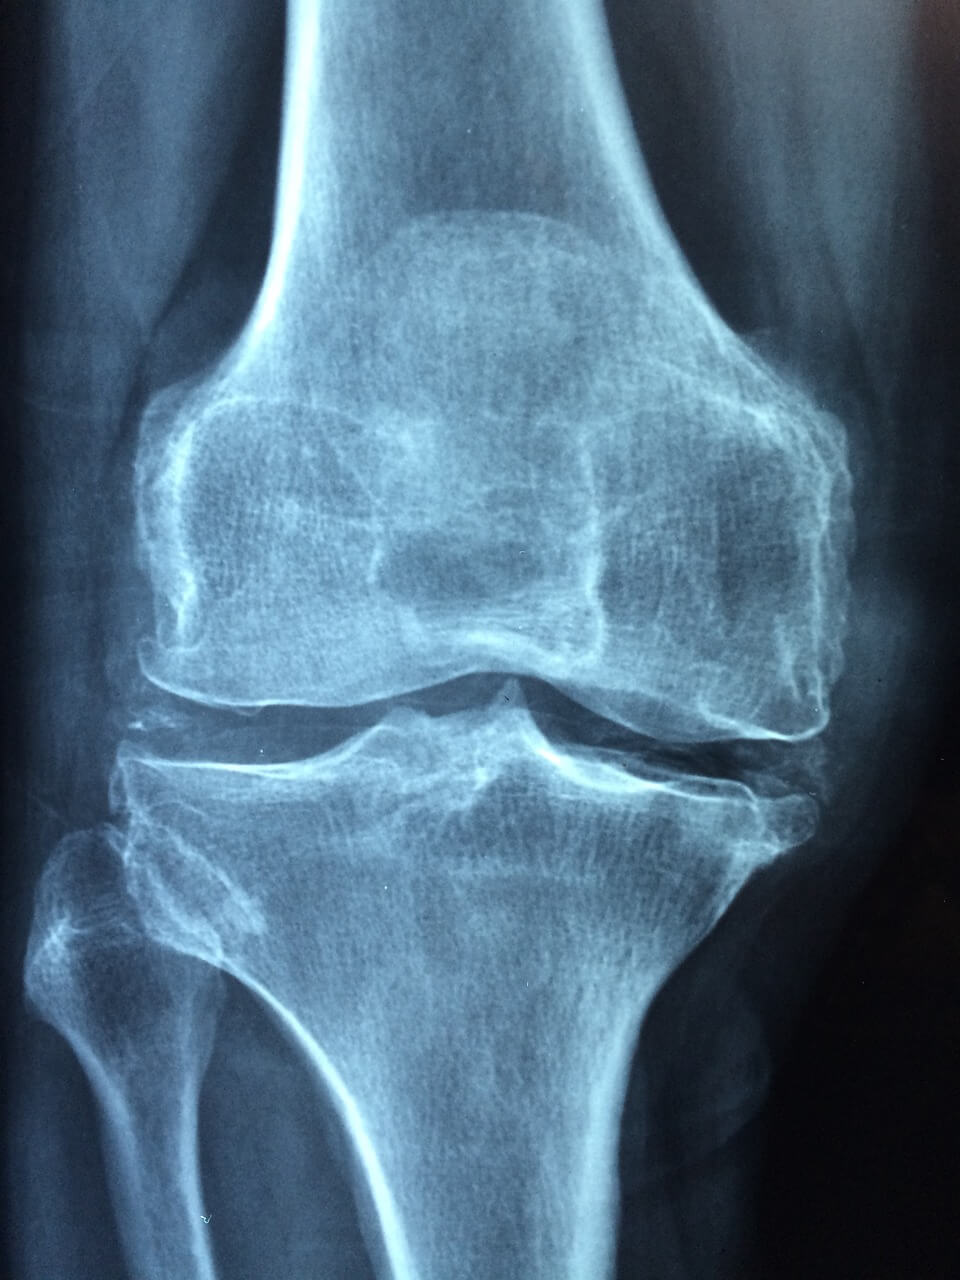

콘드로이친 C6S (Chondroitin-6-Sulfate)는 연골, 인대, 결합조직에 존재하는 황산화된 당사슬 구조의 다당류입니다. 우리 몸에서 C6S는 특히 관절의 윤활 기능, 충격 흡수, 연골 유지에 필수적인 역할을 합니다.

C6S가 부족해지면 연골이 점차 마모되어 관절이 뻣뻣해지고, 통증을 유발하는 퇴행성 관절염이나 연골 손상이 가속화될 수 있습니다.

- 무릎 관절의 뻣뻣함 및 굽힘 통증

- 계단 오르내릴 때 관절 마찰감

- 활동 후 관절에 피로감 또는 붓기

- 손목, 발목 등 작은 관절의 잦은 불편감

👉 특히 50대 이상 중장년층, 운동선수, 관절 부상 이력자들은 C6S 결핍 상태가 더 쉽게 발생할 수 있습니다.